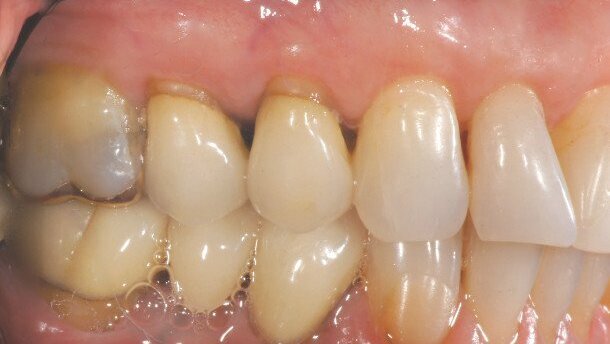

A 55-year-old woman presented requesting removal of the maxillary left bicuspid and molar crowns. Their unsightly margins and the gold restorations were visible in her smile (Figs. 1 & 2), and the patient had grown weary of their un settling and lackluster appearance. Her goal was to whiten her dull-looking teeth in order to reflect the brighter colour of her natural anterior dentition.

In-office CAD/CAM restorations (IPS e.max CAD) were discussed with and agreed to by the patient. The optical qualities of IPS e.max CAD, which include a fairly low refractive index, optimal light transmission and lifelike translucency, would provide natural appearing and highly aesthetic

Restorations.(2,3)